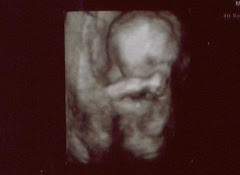

We took our childbirth classes on Friday night and Saturday. I must say that I already knew a lot of what they taught us. Watching "Birth Day" and "A Baby Story" all day for 4 months can really be educational!! However, I was a little shocked by the constant reminder that childbirth HURTS!!!!!!! As a woman, I was raised knowing that giving birth to a child was a painful experience. Why was it that this instructor felt like she needed to scare all of the poor pregnant mommies in the class? The entire way home Friday night, Phillip was reassuring me that I can do this. I will live through the pains and humiliations that come along with bringing a beautiful life into the world. Don't get me wrong...you all know that I would do anything to bring my beautiful baby Blain into the world. I just felt a little overwhelmed with the gory details. We did learn some useful information, and I feel like we are both more prepared. It was quiet funny to see Phillip's reaction to many of the topics and activities. We were probably the least engaged couple in the class. My favorite one-liner from Phillip was: "No kitchen utensils will be used in our room!!!" The lady had a rolling pen for massaging the mommy. Overall, it was a fun experience to share with Phillip. We will have many laughs over that class. :) Love from our family...AMBER

I have started to think forward to what the deliver will be like. We will both make it through...but it is a little overwhelming to think about all the details!